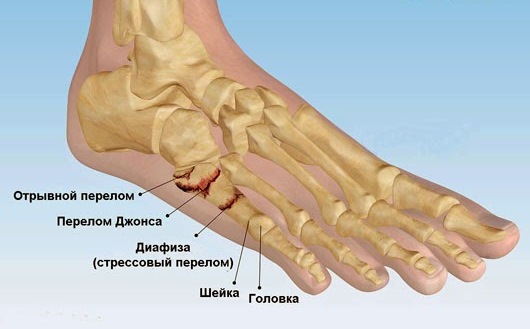

Перелом Джонса

В области травматологии существует особый тип перелома плюсневых костей, известный как перелом Джонса. Этот перелом локализуется у основания пятой плюсневой кости и отличается крайне медленным процессом сращивания отломков. У некоторых людей кость в этом районе может вообще не срастаться.

Часто, когда пациенты обращаются за медицинской помощью, им ставят ошибочный диагноз и назначают лечение растяжения связок стопы. Подобный подход может привести к серьезным последствиям.

Пятая плюсневая кость

Современная травматология и хирургия часто сталкиваются с переломами пятой плюсневой кости. Эта кость, расположенная ближе к внешнему краю стопы, подвержена различным травмам. Повреждение обычно происходит при выворачивании стопы. Клинические проявления перелома пятой плюсневой кости включают отек в области травмы и сильную боль. Пострадавший не в состоянии ходить и опираться на поврежденную ногу.

Переломы плюсневой кости могут возникать в различных местах: у основания, в средней части или на верхушке.

Виды перелома 5 плюсневой кости:

-

Отрывной перелом. Данный тип костного повреждения возникает из-за отрыва фрагмента кости под воздействием натяжения, создаваемого прилегающими сухожилиями. Чаще всего такие переломы наблюдаются у людей, которые подвернули стопу внутрь. Установить диагноз может быть сложно, особенно если травма сопровождается переломом или растяжением связок голеностопного сустава.

Перелом Джонса. Этот перелом происходит на границе между проксимальной частью диафиза и метафизом. Данная область имеет плохое кровоснабжение, что приводит к длительному или даже отсутствующему сращению костных фрагментов. Пятая плюсневая кость обладает особыми характеристиками: она имеет больший диапазон движений по сравнению с другими плюсневыми костями, что негативно сказывается на ее стабильности при травмах. Механизм повреждения заключается в приложении силы как в вертикальном, так и в медиолатеральном направлении к основанию пятой плюсневой кости, когда стопа находится в положении подошвенного сгибания. Перелом Джонса чаще всего возникает у людей, подвергающихся циклическим стрессовым нагрузкам.